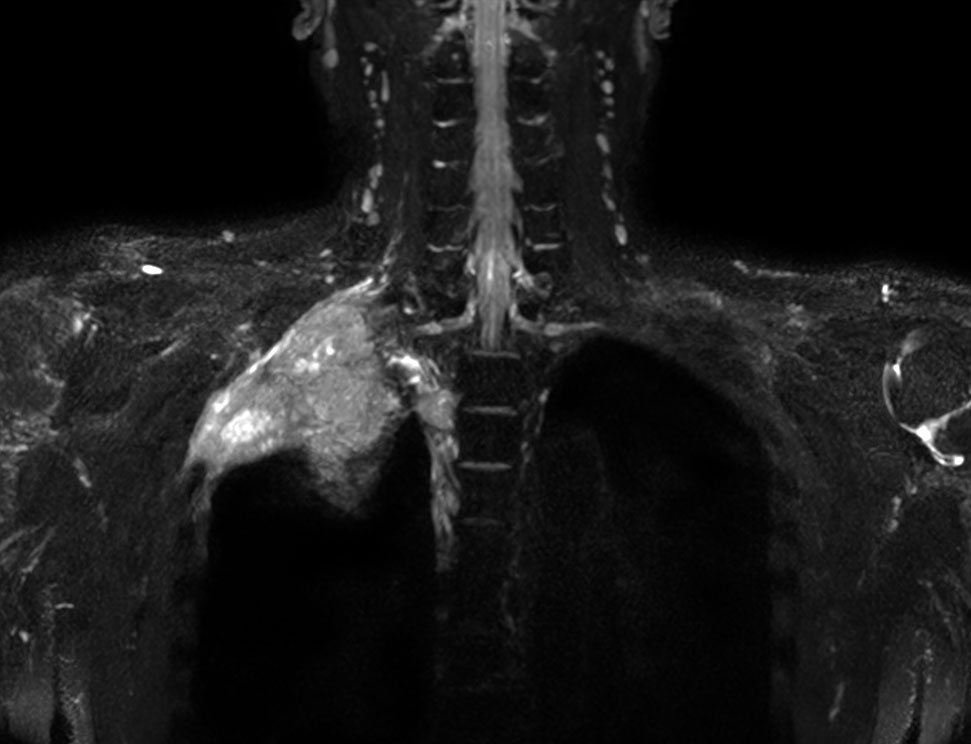

Coronal 3D NerveVIEW (MIP)